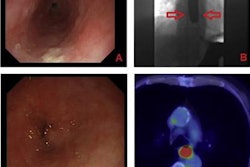

Image courtesy of Dr. David DiSantis.However, in 2019, there were 2.9 million fluoroscopy procedures performed in the U.S. DiSantis and colleagues aimed to analyze trends to identify which studies are still performed in significant volume as a guide for matching trainee education with current practice.